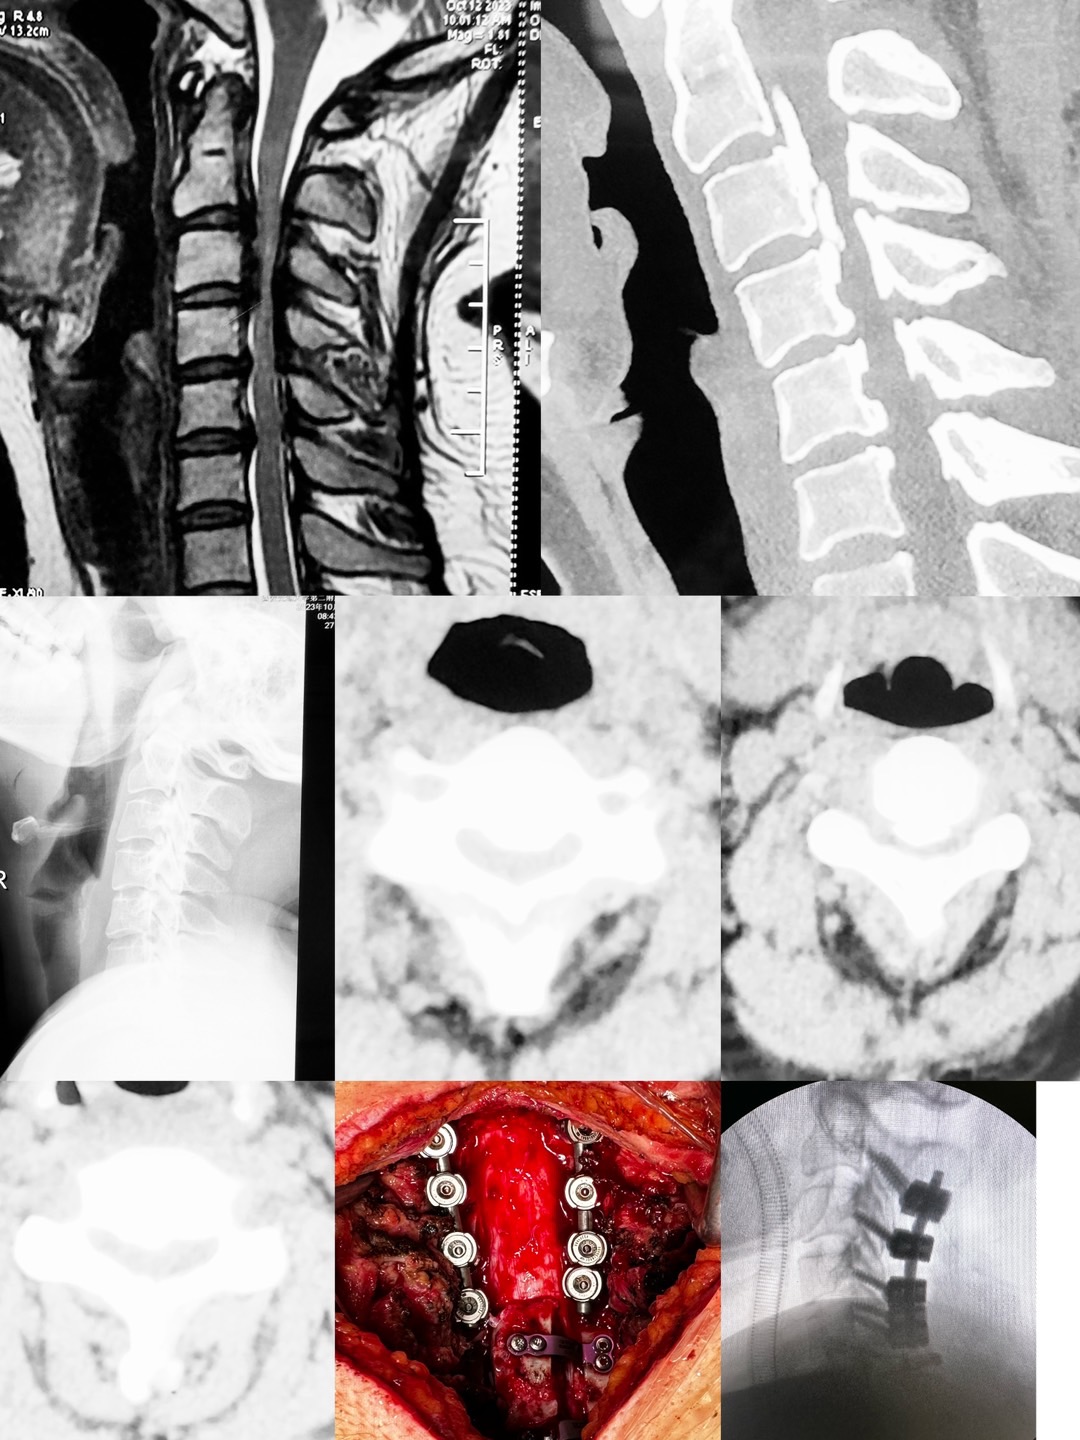

像这样的高难度颈椎手术,臧全金副主任医师带领曹凯博士、郭帅博士的团队近期已完成了多例,均取得了良好的手术效果。一例外省的颈椎肿瘤患者,慕名从省外来到骨二科,在臧全金副主任医师团队的精心治疗下,一期前后路切除肿瘤,完成颈椎重建,术后神经功能得到恢复。多例颈椎后纵韧带骨化患者,椎管内占位达到椎管前后径的70-80%,脊髓被压得只剩下一条线,臧全金带领的团队精雕细琢,为患者完成减压,术后患者从蹒跚行走到灵活小跑;颈椎间盘突出压迫脊髓瘫痪患者在臧全金团队的治疗下从卧床到下地行走…………为了解决患者的病痛,臧全金急患者之所急,近一周从家中赶往医院为两次颈椎脱位脊髓损伤患者行急诊手术,第一时间挽救患者脊髓功能。很多病例不一例数。

作为骨科最年轻的带组副主任医师,臧全金在过去的六年里带领治疗团队完成了科室的近半疑难病例及危重患者,同时精细研究业务,配备了自己的手术放大镜和术中录像系统,将手术风险、创伤降低的同时提高了治疗效果,目前颈椎前路手术可在三至四厘米切口下高质量完成的同时出血量控制在几十毫升,寰枢椎脱位手术在一小时左右完成切开复位固定,颈椎后路手术也在1.5小时左右完成,总体出血量越来越少。